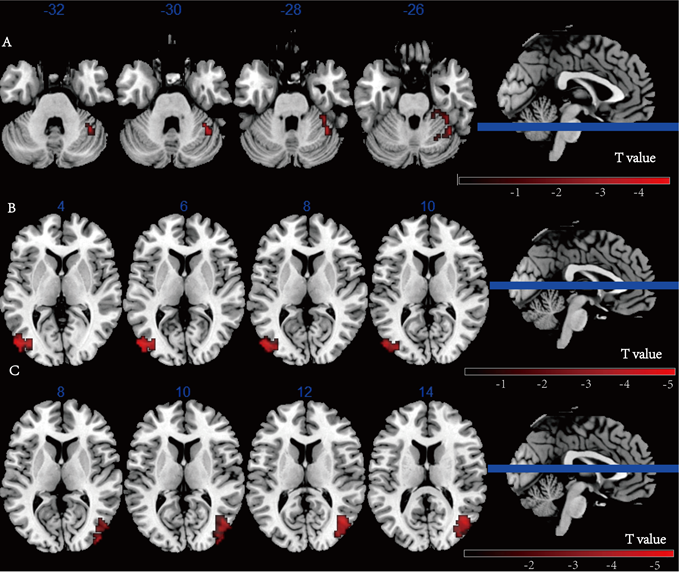

研究结果表明,相较于对照组,实验组干预后疼痛(NRS评分)改善更明显,恐惧回避情况(FABQ)也得到明显改善。干预后实验组左侧DLPFC与右侧小脑及双侧枕回之间的功能连接显著增强(图1)。相关性分析表明,NRS得分与左侧DLPFC和右侧小脑、双侧枕叶回的功能连接之间存在显著负相关(图2)。本研究提示iTBS可能通过强化DLPFC-小脑-枕回环路的功能连接,增强疼痛抑制与认知调控,从而缓解慢性腰痛症状。

图1. 实验组干预前后的脑功能连接改变(数据由分析测试中心磁共振成像机组提供)

分析测试中心磁共振成像机组为基于64通道高密度头颈联合线圈的Resting(静息态功能磁共振成像)数据采集提供了技术支持,相关数据均在中心3T磁共振成像(Siemens 3T Prisma)实验室完成采集,为王楚怀教授团队探究间歇性θ节律刺激对慢性腰痛患者疼痛缓解的效果及其潜在机制提供了重要的数据支撑(图1)。